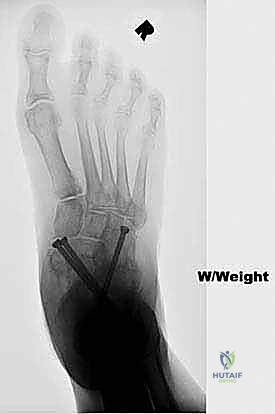

FIG 3 • Radiographs of a 56-year-old diabetic woman with severe pes planovalgus deformity and gross subluxation of the subtalar and transverse tarsal joints radiographically.

Standard weight-bearing radiographs of both the foot and ankle are critical in evaluating severe pes planovalgus deformities. The foot films will determine the amount of subluxation or dislocation of the subtalar and transverse tarsal joints that must be corrected. They can also determine whether there is deformity or bone loss that demands the addition of structural bone grafts. The ankle radiographs are required to confirm that the severe heel valgus is isolated to the hindfoot. Occasionally, severe valgus hindfoot deformity leads to increasing deltoid ligament incompetence, creating a valgus tilt of the talus within the ankle mortise. Deltoid ligament incompetence and valgus tilt of the ankle may necessitate surgical correction of the ankle as well should hindfoot realignment with triple arthrodesis fail to rebalance the tibiotalar joint ( FIG 3 ).

- All talonavicular and subtalar joints healed ( FIG 4 ).

Radiographic Correction Was Comparable To Previous Series Describing Traditional Two-Incision Triple Arthrodesis.

In a cadaver study, 90% of the calcaneocuboid joint articular surface was able to be prepared successfully from the medial incision.

- Two of the 17 patients (12%) developed a nonunion of the calcaneocuboid joint. Neither of these was symptomatic.

- Three patients developed valgus ankle arthritis after successful triple arthrodesis. These were managed with total ankle replacement in two patients and ankle arthrodesis in one patient.

Seventeen patients underwent single-medial-incision triple arthrodesis.

All 17 demonstrated clinical improvement in alignment and pain relief.

FIG 4 • After single-medial-incision triple arthrodesis, the patient shown in Figure 3 had excellent correction of her deformity without wound-healing complications.